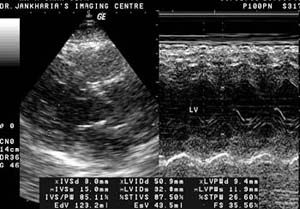

Echocardiography

What is echocardiography?

It is a method of studying the heart and the adjacent great vessels

using ultrasound.

What is it used for?

Echocardiography is used to study the structure and function of the

chambers of the heart, the integrity of the valves and the coverings of

the heart.

Does color Doppler help?

It allows better visualization of the vessels and the chambers of the

heart